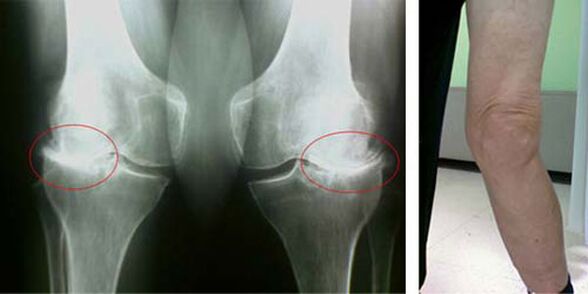

Belauneko artikulazio osasuntsu batean, kartilagoa hezurrak ukitzen uzten ez duen estaldura moduko bat da, beraz, ibiltzean kalteak egiteko aukera ezabatzen du. Gaixotutako kartilagoak ezin dio funtzio honi aurre egin, beraz, mugimenduan zehar artikulazioetan zurruntasunaren seinaleak agertzen dira, minarekin batera. Baldintza hau iraunkor bihurtzen da barne-aldaketa patologikoen ondorioz, kartilago-ehunaren mehetasunak hezurra loditzen duenean eta hezur-esproiak agertzeko baldintzak sortzen dituenean - osteofitoak, mina akutua eragiten dutenak.

Belauneko artikulazioko artrosia bezalako patologia baten hasierako faseak ez dira inolaz ere ikusten. Hala ere, denbora jakin baten ondoren, gaixoak belauneko deformazioaren seinaleak nabaritzen ditu, baita beheko hankaren ardatzean (barrurantz zuzenduta) kurbadura bereizgarria ere. Hanka tolestu behar duzunean ere kurrixka bat dago.

Mina egoteak, belauneko mugimendu mugatuak pertsona batek medikua ikusi eta azterketa bat egiten du. Horretarako, probak gainditu eta gaixotutako artikulazioaren erradiografia egin behar du. Neurri hauek belauneko artikulazioaren artrosia baieztatzeko nahikoa ez badira, erresonantzia magnetikoko irudia egiten da. Bildutako datuen arabera, medikuak tratamendu metodorik onenak aukeratzen ditu.